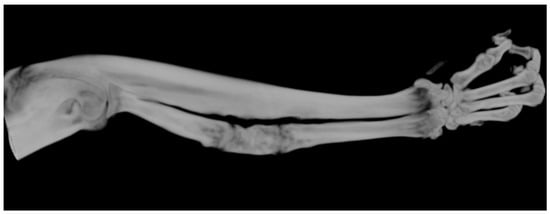

Following the imaging exploration by μCT and 3D image reconstruction through specialized software Vox CT Software Version 3.3.0 r1412, samples were randomly and blindly explored by two experienced medical imaging experts who generated a percentage score for the newly formed callus (Figure 5). Following averaging of the results from the two experts, percentage values for each sample were obtained, as displayed in Figure 4. These individual values were assigned as the total callus volume and were calculated as a percentage of the total volume of the induced bone defect. Selected images from each study group that were examined and evaluated after 3D reconstruction by Vox CT Software Version 3.3.0 r1412 are displayed in Figure 6, Figure 7, Figure 8 and Figure 9.

Figure 6. A 3D μCT image of the best healing sample from the ABG group, where the sample accounted for 100% bone healing; mineralization and radiotransparency similar to healthy bone may be observed.